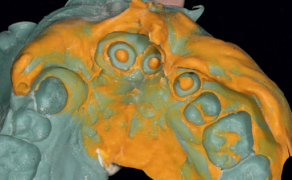

Aparaty zdejmowane składają się z części akrylowej oraz elementów drucianych. Elementy druciane stosowane w zdejmowanych aparatach ortodontycznych są wykonane ze stali sprężystej hartowanej twardej o średnicy od 0,3 do 1,5 mm. Wśród elementów drucianych wyróżnia się: łuki, klamry, sprężyny oraz elementy dodatkowe. Szczegółowy podział zaprezentowano na ryc. 1.

Elementy te dalej mogą zostać podzielone na utrzymujące, takie jak: klamry, podpory zgryzowe, bolce międzyzębowe, elementy aktywne, wśród których wyróżnia się sprężyny oraz elementy dodatkowe, które mogą zostać wykorzystane jako elementy aktywne – łuki wargowe, peloty, wąsy oraz zapory dla języka. Niektóre z powyższych elementów mogą zostać wykorzystane [...]